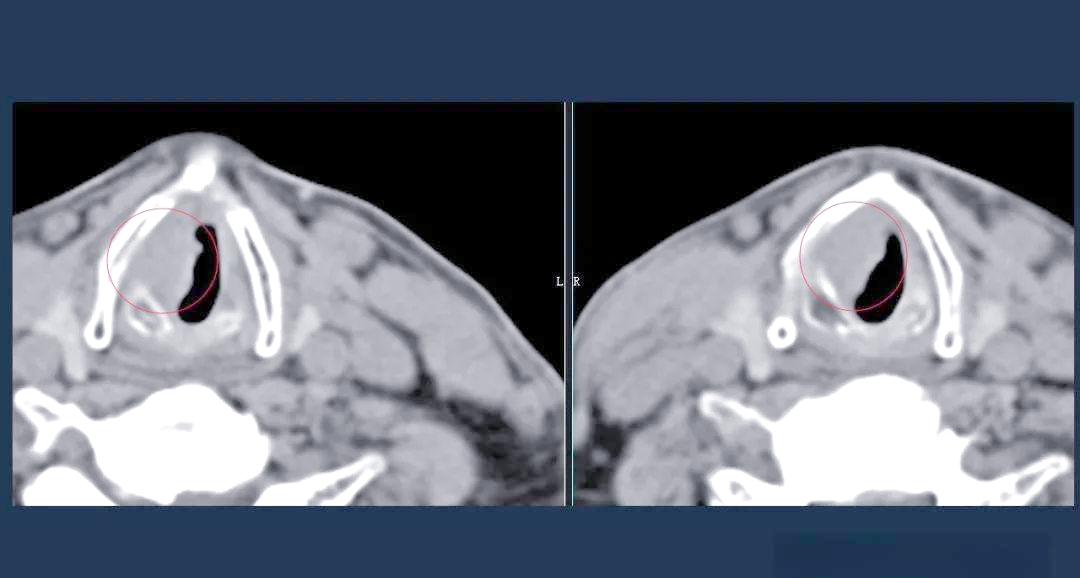

喉癌的ct,mri诊断